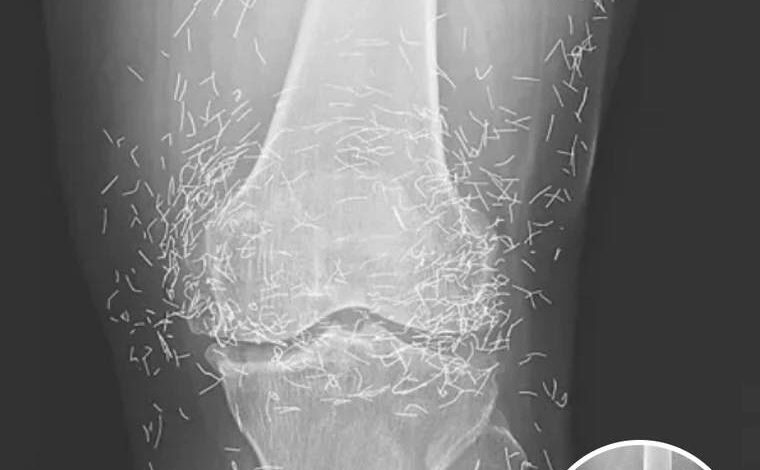

GOLD NEEDLE MYSTERY Doctors Shaken By Secret Objects Hidden Inside Womans Knee XRay For Decades

When a 65-year-old woman walked into a medical clinic in South Korea complaining of chronic, debilitating joint pain, the physicians expected to see the standard markers of a long-term degenerative condition. They anticipated the narrowing of joint spaces, the telltale bone spurs, and the loss of cartilage that defines a life lived with osteoarthritis. However, the moment the X-ray film was developed, the medical team was met with a sight that defied conventional clinical experience. Staring back at them from the glowing screen were hundreds of tiny, hair-thin gold needles, meticulously embedded deep within the soft tissue and muscle surrounding her knees. This was not a sudden injury or a freak accident; it was the physical map of a years-long battle against pain that had pushed a patient to seek an extreme form of alternative relief.

Desperate for a solution that didn’t involve a chemical trade-off, she turned to the deep-rooted traditions of her culture. In many parts of Asia, particularly South Korea, acupuncture is not just a secondary option; it is a primary pillar of the healthcare system. However, the specific procedure she underwent went far beyond the typical temporary insertion of needles. In a practice known as gold thread or needle implantation, practitioners intentionally leave the needles inside the body. The theory behind this controversial method is that the gold provides continuous, long-term stimulation to the acupuncture points, theoretically offering a permanent blockade against the pain signals caused by arthritis. To the patient, it was a promise of a life without pills; to the doctors who saw the X-ray decades later, it was a potential medical time bomb.

Beyond the biological risks, these hidden needles pose a significant challenge to modern diagnostic technology. In the field of radiology, metal is a notorious disruptor. These hundreds of gold fragments create “artifacts” on imaging, appearing as bright white streaks that can obscure the very anatomy doctors need to see. This makes it incredibly difficult to track the progression of the patient’s arthritis or to screen for other underlying issues like bone tumors or fractures. The presence of metal also creates a dangerous barrier to one of the most powerful tools in medicine: the MRI. Because an MRI uses incredibly strong magnets, any metallic object inside the body can be subjected to intense force. If a patient with gold needles were to accidentally undergo an MRI, the magnetic pull could cause those needles to migrate through the tissue, potentially puncturing nerves, slicing through tendons, or tearing open major blood vessels, leading to life-threatening internal bleeding.

The woman’s case, which was eventually documented in the prestigious New England Journal of Medicine, has become a landmark cautionary tale for healthcare providers and patients alike. It highlights the profound disconnect that can sometimes exist between traditional beliefs and modern safety standards. While the woman may have felt an initial sense of relief from the “continuous stimulation” of the gold, she was ultimately left with a knee joint that was a literal minefield of metal. The X-rays serve as a haunting visual reminder that our bodies are not meant to be permanent containers for external materials, no matter how precious the metal may be.